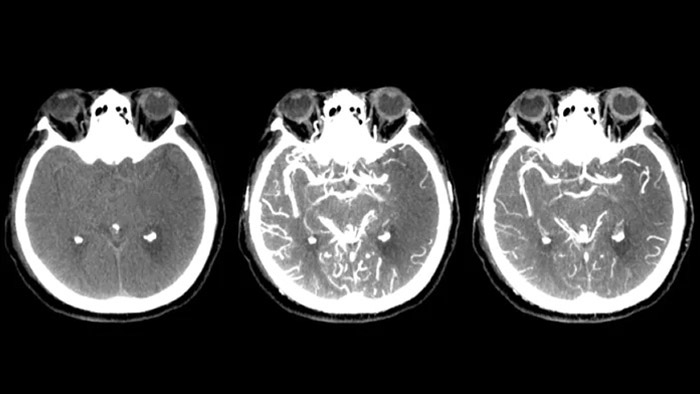

CTライクイメージ

SmartCT Soft Tissueは、軟部組織をCTのように可視化し、3つの方法で脳卒中診断を支援します。非造影スキャンは、早期虚血性変化の検出に役立ちます。造影スキャンの早期フェーズでは、近位閉塞の識別に役立ちます。造影スキャンの後期フェーズでは、側副路の検出をサポートします。

SmartCT Soft Tissue

SmartCT Sofy Tissue撮影にて、出血の有無等、治療後の確認を行います。